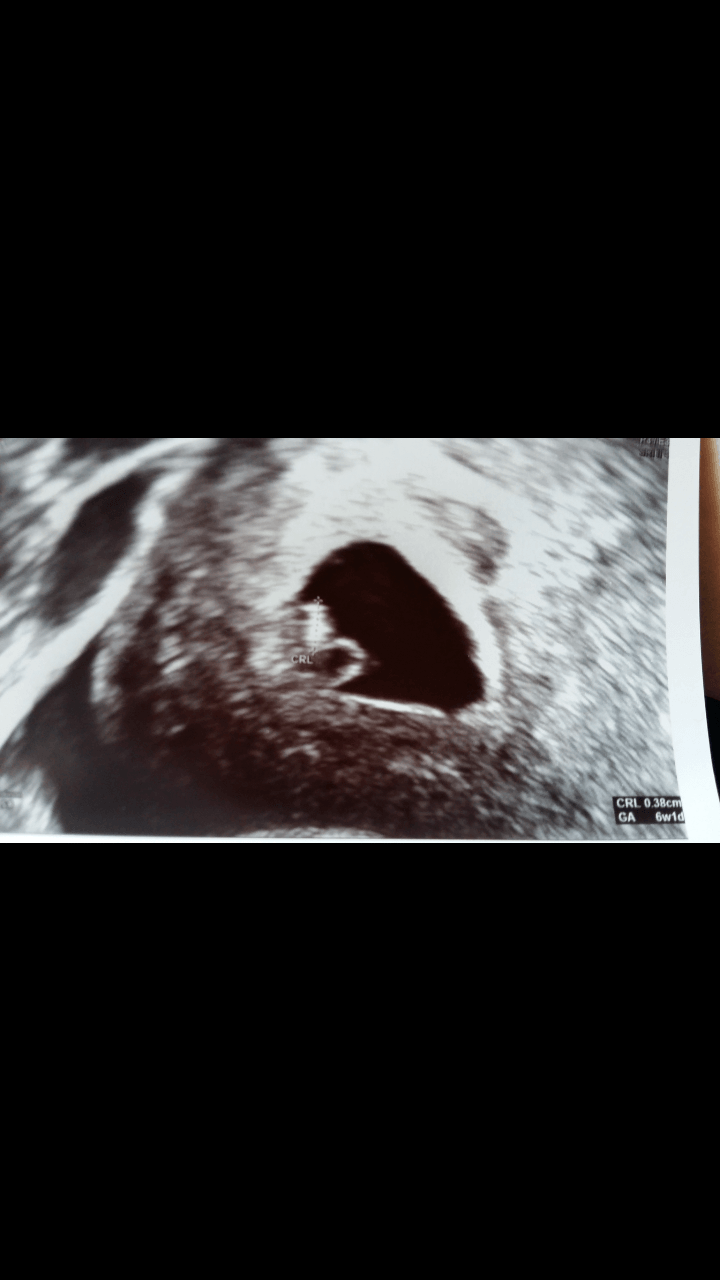

Byłam dzisiaj na USG i wszystko jest w porządku. Fasola ma 3,8 mm, serduszko bije. Ale mi ulżyło! Wg USG to 6 tydz 1 dzień i termin na 22 lutego.

Fasolka:

Zobacz załącznik 812842